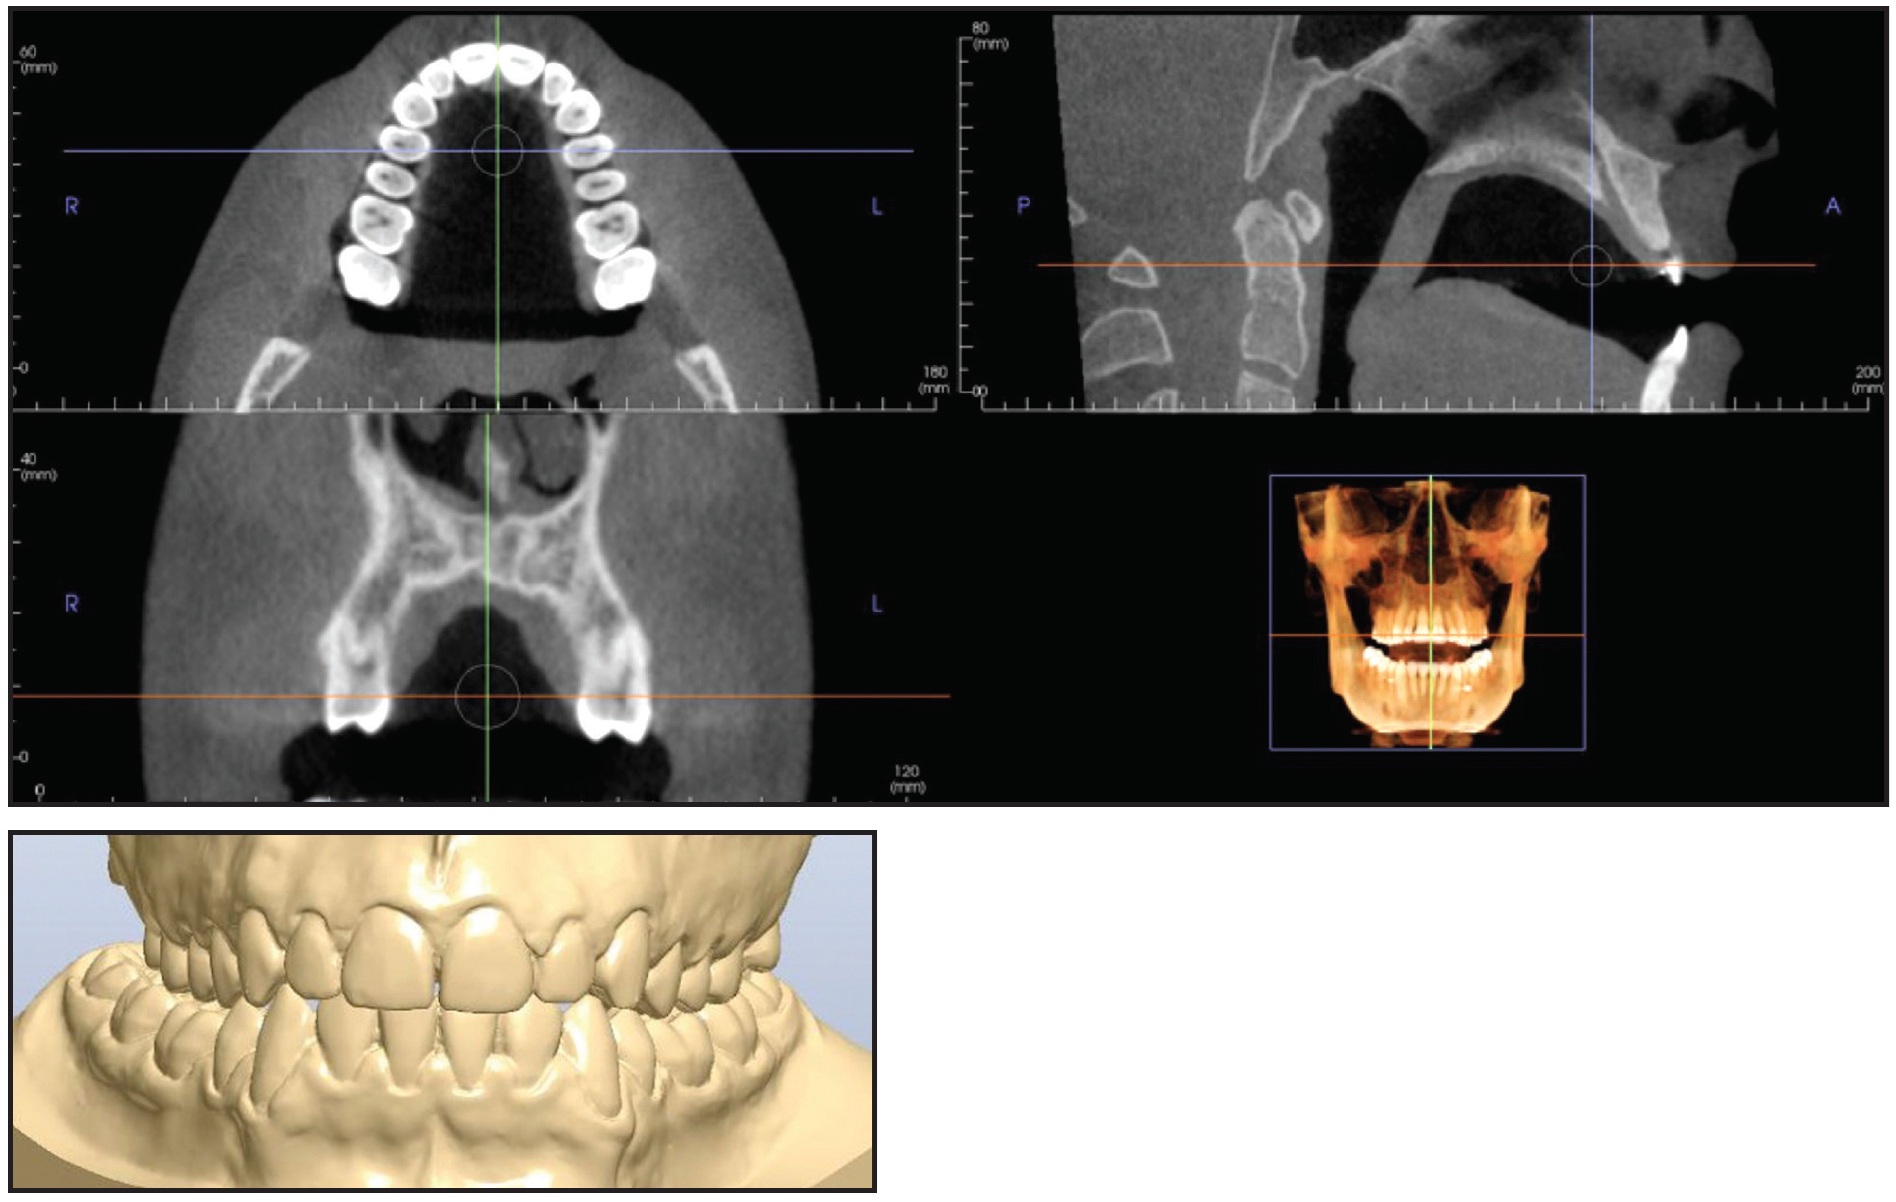

A 24-year-old male presented with a skeletal and dental Class III malocclusion (Fig. 10A). Bimaxillary orthognathic surgery had been planned when the patient was 18 years old. At that time, both lower first premolars had been extracted, and both arches had been leveled and aligned. The patient delayed the orthognathic surgery and returned six years later to continue treatment.

Fig. 10 Case 2. 24-year-old male patient with skeletal and dental Class III malocclusion and maxillary deficiency before treatment (continued in next image).

A maxillary deficiency was apparent from a frontal view. The dental midlines were coincident with the facial midline, and the lower third of the face was well balanced with the central and upper thirds. The patient exhibited a concave profile with a protrusive mandible and a backwardly positioned maxilla. Intraoral examination found Class III molar and canine relationships on the right and left sides, with no crowding in either arch (Fig 10B). Two miniscrews, which had been used as anterior anchorage for the previous orthodontic treatment, were present in the lower arch. Except for the lower first premolars, all teeth were present.

Cephalometric analysis (Table 2) confirmed a Class III relationship (ANB = −3.3°, Wits appraisal = −9mm). The skeletal growth pattern was normodivergent (FMA = 23.4°). The upper incisors were mesially inclined with respect to the palatal plane (U1-PP = 116.7°), and the lower incisors were normally inclined (IMPA = 87.9°).

Fig. 10 (cont.) Case 2. 24-year-old male patient with skeletal and dental Class III malocclusion and maxillary deficiency before treatment. (Lower first premolars were extracted six years earlier during prior treatment.)

Axial CBCT slices at the upper canines and premolars and at the furcation of the first molars confirmed the maxillary transverse deficiency and the bilateral crossbite, which could also be observed in a diagnostic simulation of the proposed maxillary advancement surgery (Fig. 11).

Fig. 11 Case 2. Transverse maxillary deficiency and bilateral crossbite apparent in cone-beam computed tomography and in diagnostic simulation of maxillary advancement surgery.

Because both the upper and lower arches had been leveled and aligned, the front teeth were correctly inclined, and the Class III molar and canine relationships were symmetrical, a “surgery first” approach was chosen to correct the transverse discrepancy. In consultation with the maxillofacial surgeon, we planned a noninvasive skeletal maxillary expansion with a boneborne RME. Because of the narrow and high palatal vault, a TSE was used with the MAPA System.

The optimal sites for miniscrew insertion were identified on the CBCT scan, considering the thickness and width of the palatal vault (Fig. 12).

Fig. 12 Case 2. Virtual programming of miniscrew insertion using DICOM images.